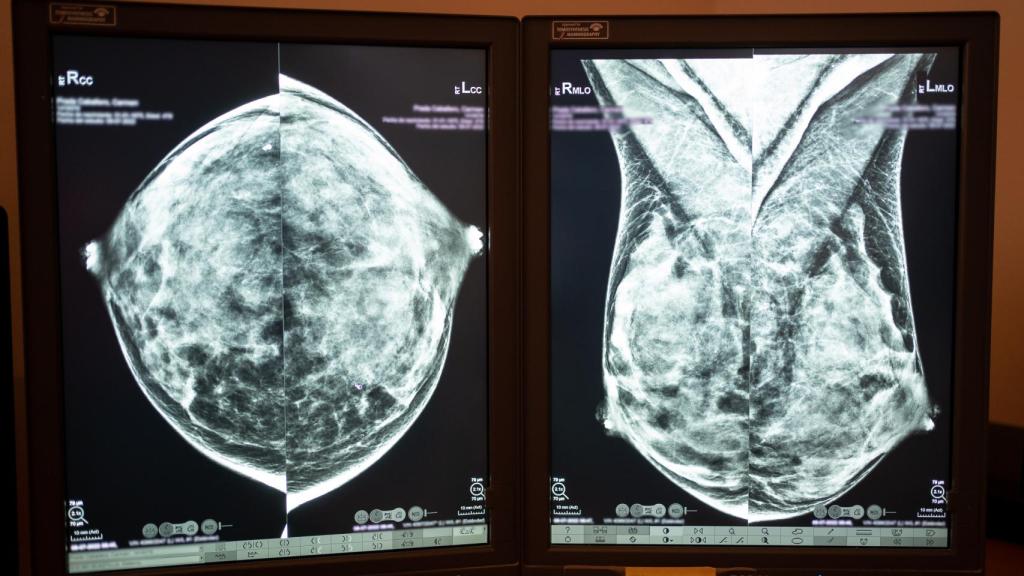

Una prueba de imagen de una mama.

Una prueba de imagen de una mama. Sara Fernández.